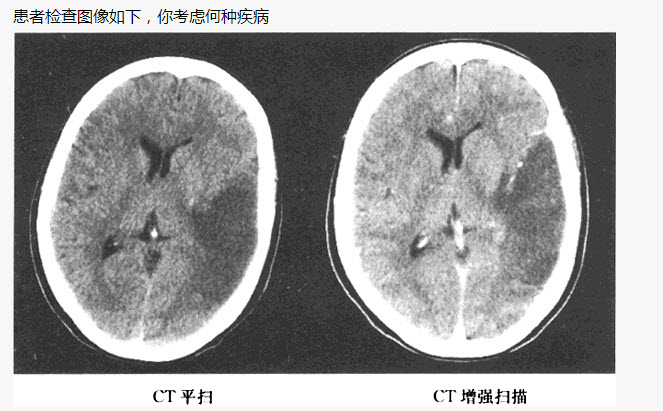

患者,女,80岁,被人发现昏迷,大小便失禁10小时入院。体格检查:血压180/100mmHg,心率约110次/分,有房颤,体温37℃,浅昏迷,右侧肢体未见自主活动,肌力增高,Babinski征阳性,GCS=E2+V1+M3=6分,有风湿性心脏病和房颤病史,既往超声检查有二尖瓣赘生物。

第2题,共2个问题

(单选题) 患者检查图像如下,你考虑何种疾病()

A:脑出血

B:脑梗死

C:脑动静脉畸形

D:脑膜炎

E:星形细胞瘤

F:脑膜瘤压迫静脉窦